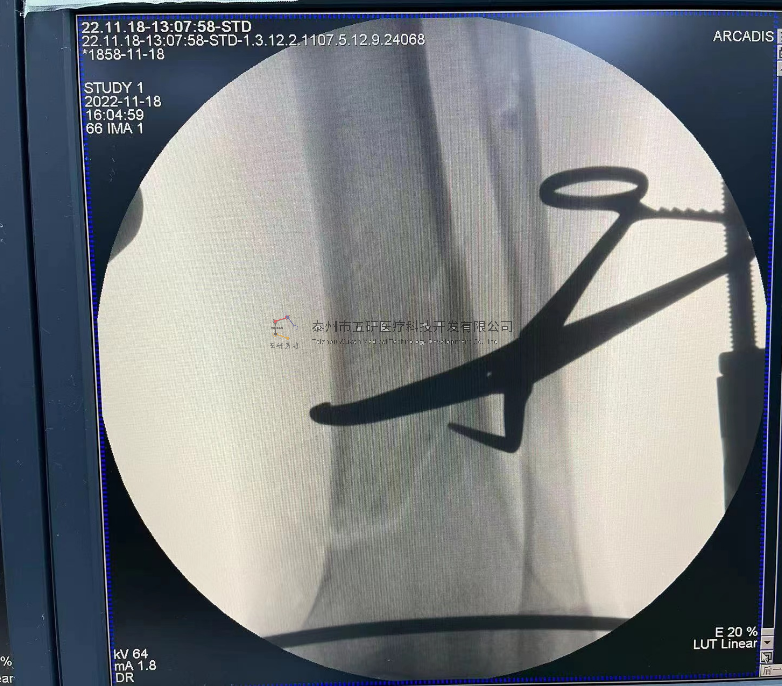

采用常規(guī)方法固定,自掌骨尺側(cè),約基底稍偏遠(yuǎn)處穿入螺紋針。

1.webp.jpg

外架馬蹄環(huán)穿過骨針,更方便調(diào)整固定角度。